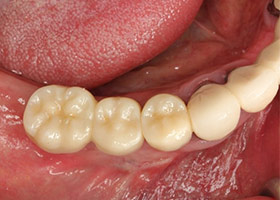

13.病患恢復健康牙周與牙齒。

14.病患恢復正常咬合功能。